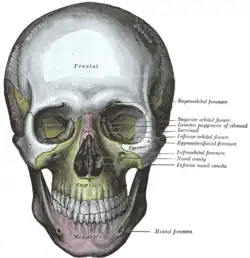

Crânio de frente. Parede medial da órbita esquerda.

Parede medial da órbita esquerda. Base do crânio. Superfície superior.